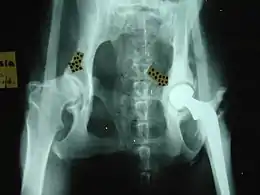

- For hip dysplasia:

- Femoral head osteotomy

- Triple pelvic osteotomy

- Hip replacement